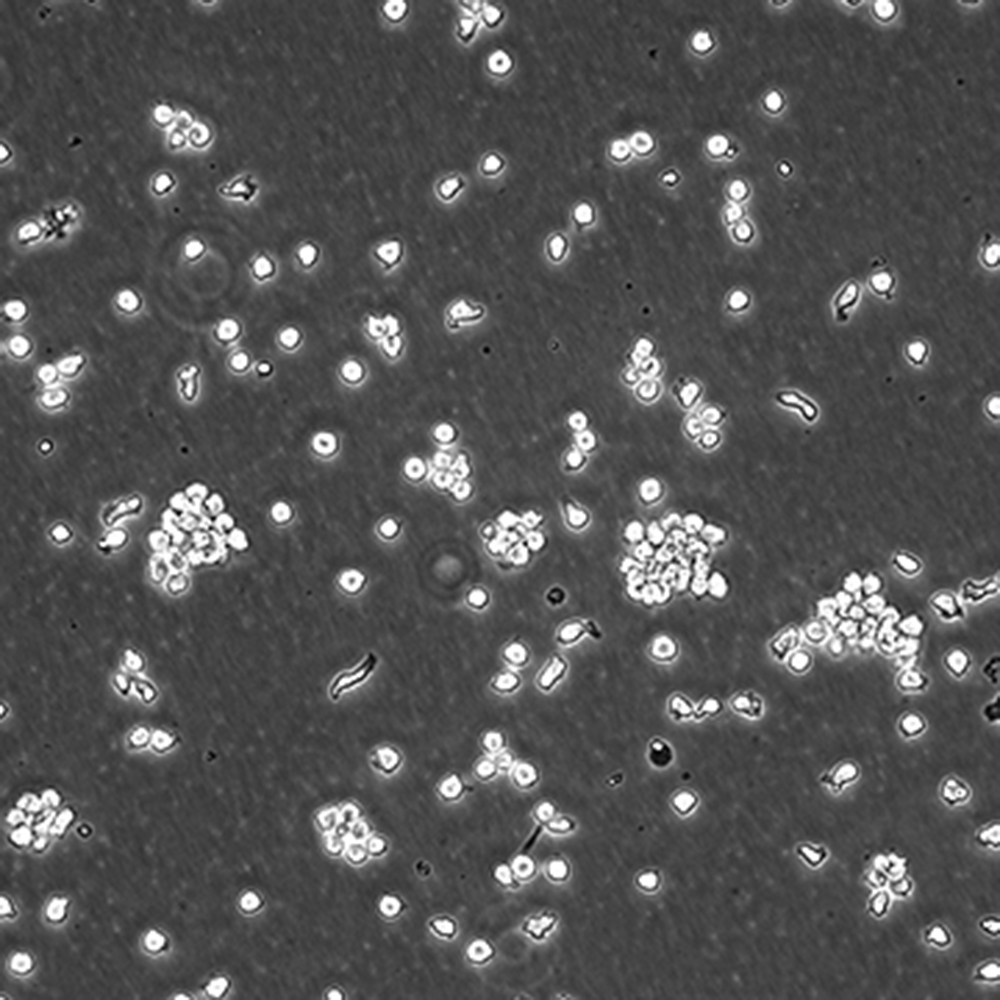

產品名稱 SUP-T1

中文名稱 人T淋巴細胞瘤細胞

組織來源 T淋巴瘤細胞;男性

生長特性 懸浮

培養(yǎng)基 1640,90%;FBS,10%;雙抗。

傳代方法 Maintain cultures at a cell concentraion between between 1 X 10(5) and 1 X 10(6) viable cells/ml.

培養(yǎng)條件 Atmosphere: Air, 95%; CO2, 5%。Temperature: 37℃